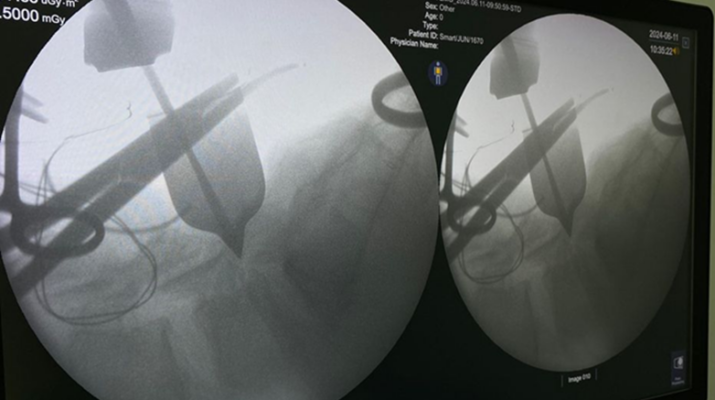

Foi realizado um procedimento cirúrgico chamado de laminectomia lombar, que alivia a pressão sobre um nervo lesionado e a medula espinhal

Para solucionar o problema, os médicos do Hospital Regional Justino Luz realizaram um procedimento cirúrgico chamado de laminectomia lombar, que alivia a pressão sobre um nervo lesionado e a medula espinhal.